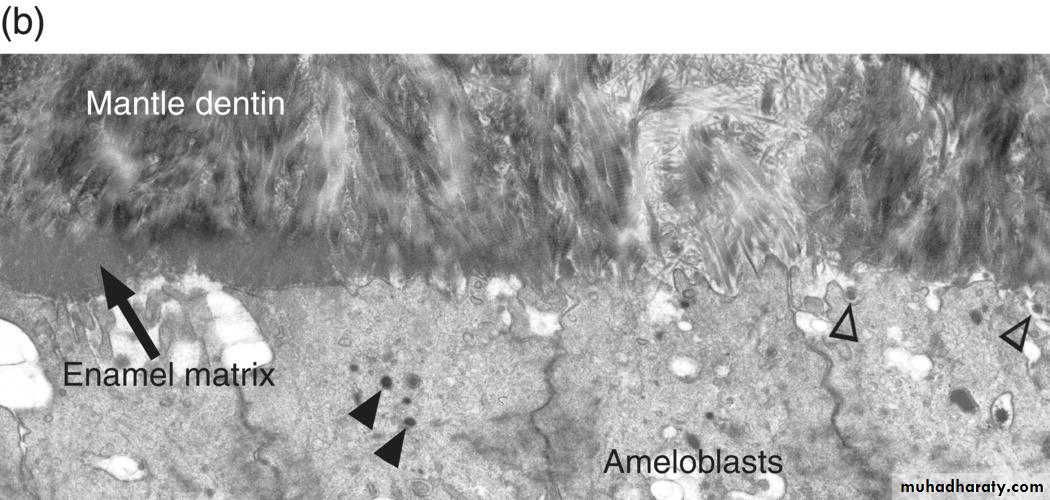

The ameloblasts start their secretory activity after a thin layer of dentin has been laid down, so a thin continuous layer of enamel is formed along the dentin. This is called the dentinoenamel membrane.The freshly secreted E. matrix contain 30% minerals as hydroxyapatite crystals,and 70% water ,and E. proteins.

Ameloblastin and enamelin help in crystal growth and nucleation. When the first layer of E. is laid down , ameloblasts will begin to retreat from DEJ towards E. surface and begins to secrete the next layer of Enamel.Enamel matrix appear as a deep staining layer in H& E staining sections. Ameloblasts secrete the E. in rods or prisms , the intially secreted E. matrix is described as rodless or prismless E.

When the first layer of dentin is formed ,it induces the adjacent preameloblasts to complete their differentiation into ameloblasts which secrete enamel. Secretory ameloblasts are polarized tall columnar cells with Tome’s processes ( conical shaped processes )at their distal ends .Tome’s processes interdigitate with the surface of the forming enamel giving it a picket fence appearance.

Tome’s processes determine the orientation of newly formed (nucleated) enamel hydroxyapatite crystals .Organelle content of secretoty ameloblasts is mainly protein synthesizing organelles i.e. Golgi complex and granular endoplasmic reticulum. Numerous mitochondria and secretory granules are also present.

Junctional complexes,tight junctions and desmosomes are present at the distal and proximal ends of ameloblasts.